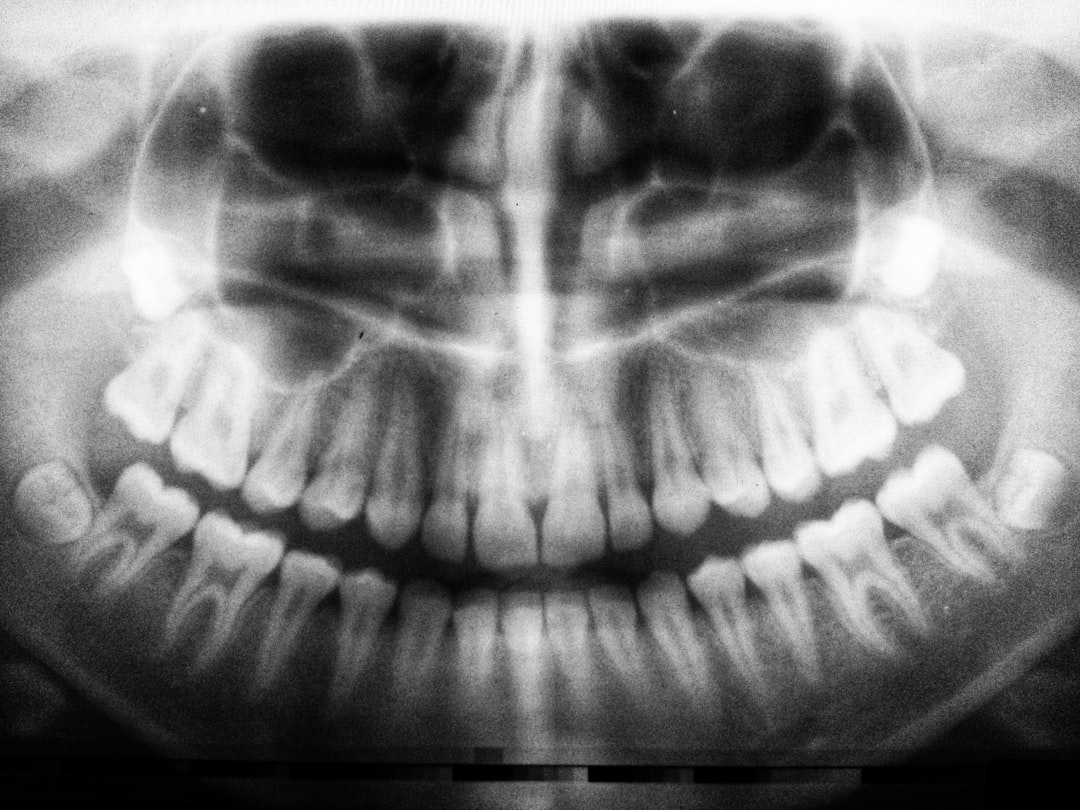

라이나생명 치아치료는 여러 가지 보장 내용을 통해 우리의 걱정을 덜어줍니다. 첫 번째로, 일반적인 치료에 대한 보장이 있습니다. 여기에는 충치 치료, 신경치료 등 기본적인 치과 치료가 포함됩니다. 라이나생명 치아치료는 이러한 기본적인 치료를 보장하여 부담을 느끼지 않도록 합니다. 그리고 이 외에도 다양한 치료 방식이 포함되어 있는 점이 특징입니다.

| 보장 항목 | 상세 내용 |

|---|---|

| 일반 치료 | 충치 치료, 신경 치료 등 |

| 미용 치료 | 치아 미백, 라미네이트 등 |

| 정기 검진 | 정기적인 치과 검진 비용 보장 |